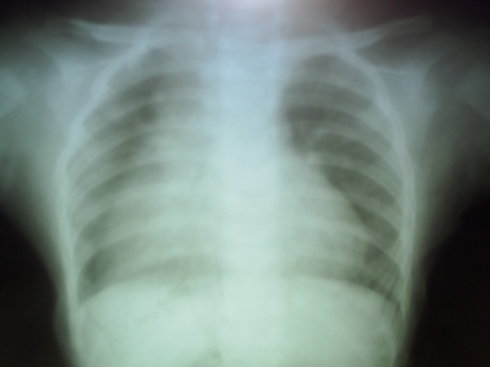

气紧,咳,无发热等异常,其他情况较好。

纵膈影增宽,右侧较平直,建议进一步检查除外纵膈或心血管病变。

卧位胸片纵膈影可增宽的,它包括胸腺及心脏影。本病例两肺门影无增大、增浓,可能是正常的。建议结合临床,必要时进一步检查。

体位因素,左右不对称,暂无明显异常,复查吧。

考虑胸腺影,必要时ct检查

右侧纵膈影增宽,建议ct检查。